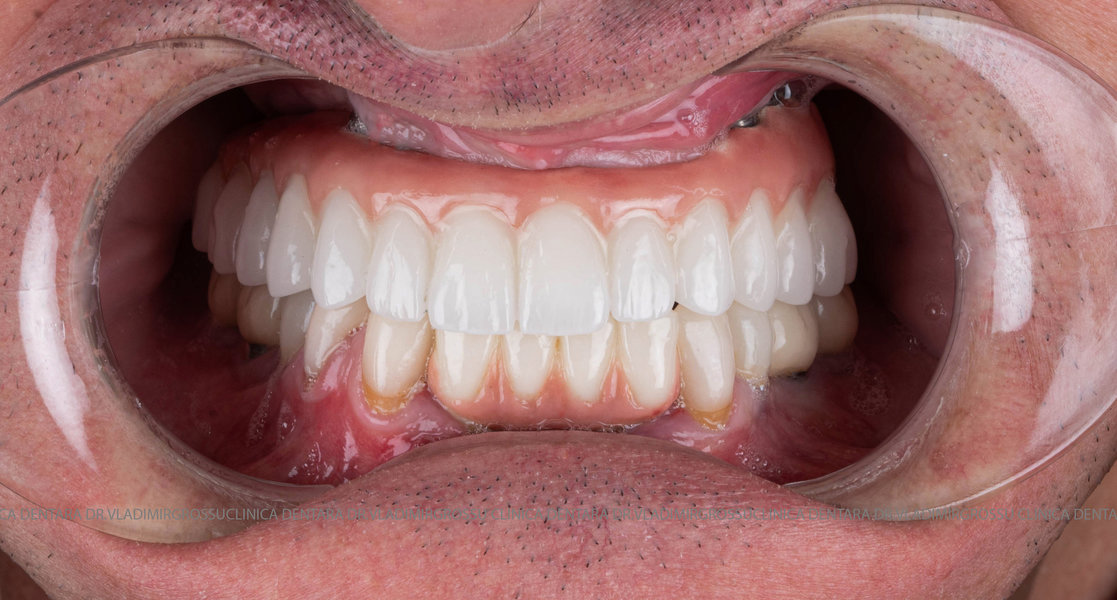

Cazuri clinice conceptul All-on-6